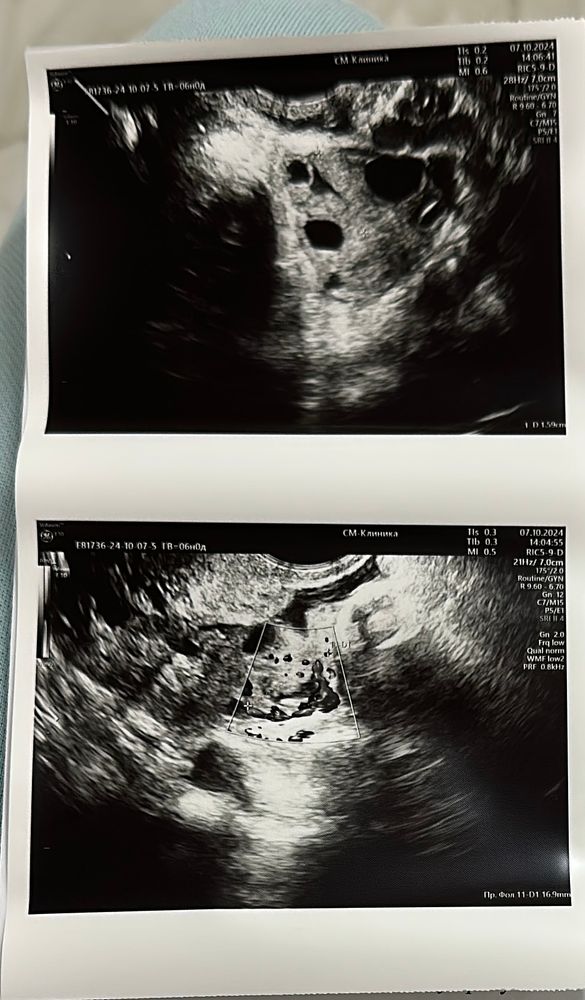

Фолликулометрия. Стимуляция овуляции. Два фолликула лопнуло

Прекрасный протокол УЗИ, все отлично и шансы высокие!) у меня яичники на стимуляцию не ответили, фолликулы так и не выросли 🥺

Хороший у вас эндометрий. Не знаю почему она сказала так. Вот у меня 6.2 был эндометрий на 11 день цикла и уже овуляция была

Z, Спасибо за ваш ответ, я вот сама удивилась, мне казалось, что таким эндометрий и должен быть, трехслойный в районе 10 мм

Замечательный эндометрий и, да О была день-два назад (жидкость в позадиматочном пространстве)